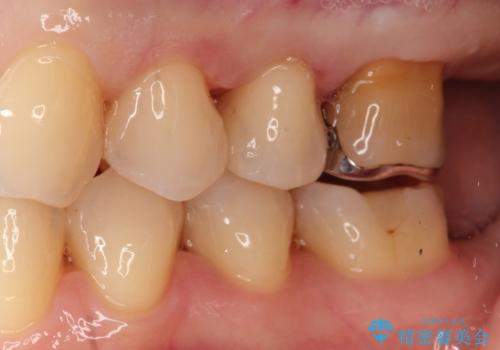

装着したセラミックインレーは、隣り合う天然歯と見分けがつかないほど自然な色調と透明感を再現しています。また、セラミックはプラーク(歯垢)が付着しにくく、適合性が非常に高いため、二次的な虫歯の予防にも大きく貢献します。

お口を開けた際に目立っていた銀色の部分が解消され、清潔感のある明るい口元になりました。金属アレルギーの心配もなく、健康的で美しい状態を長期的に維持することが可能です。